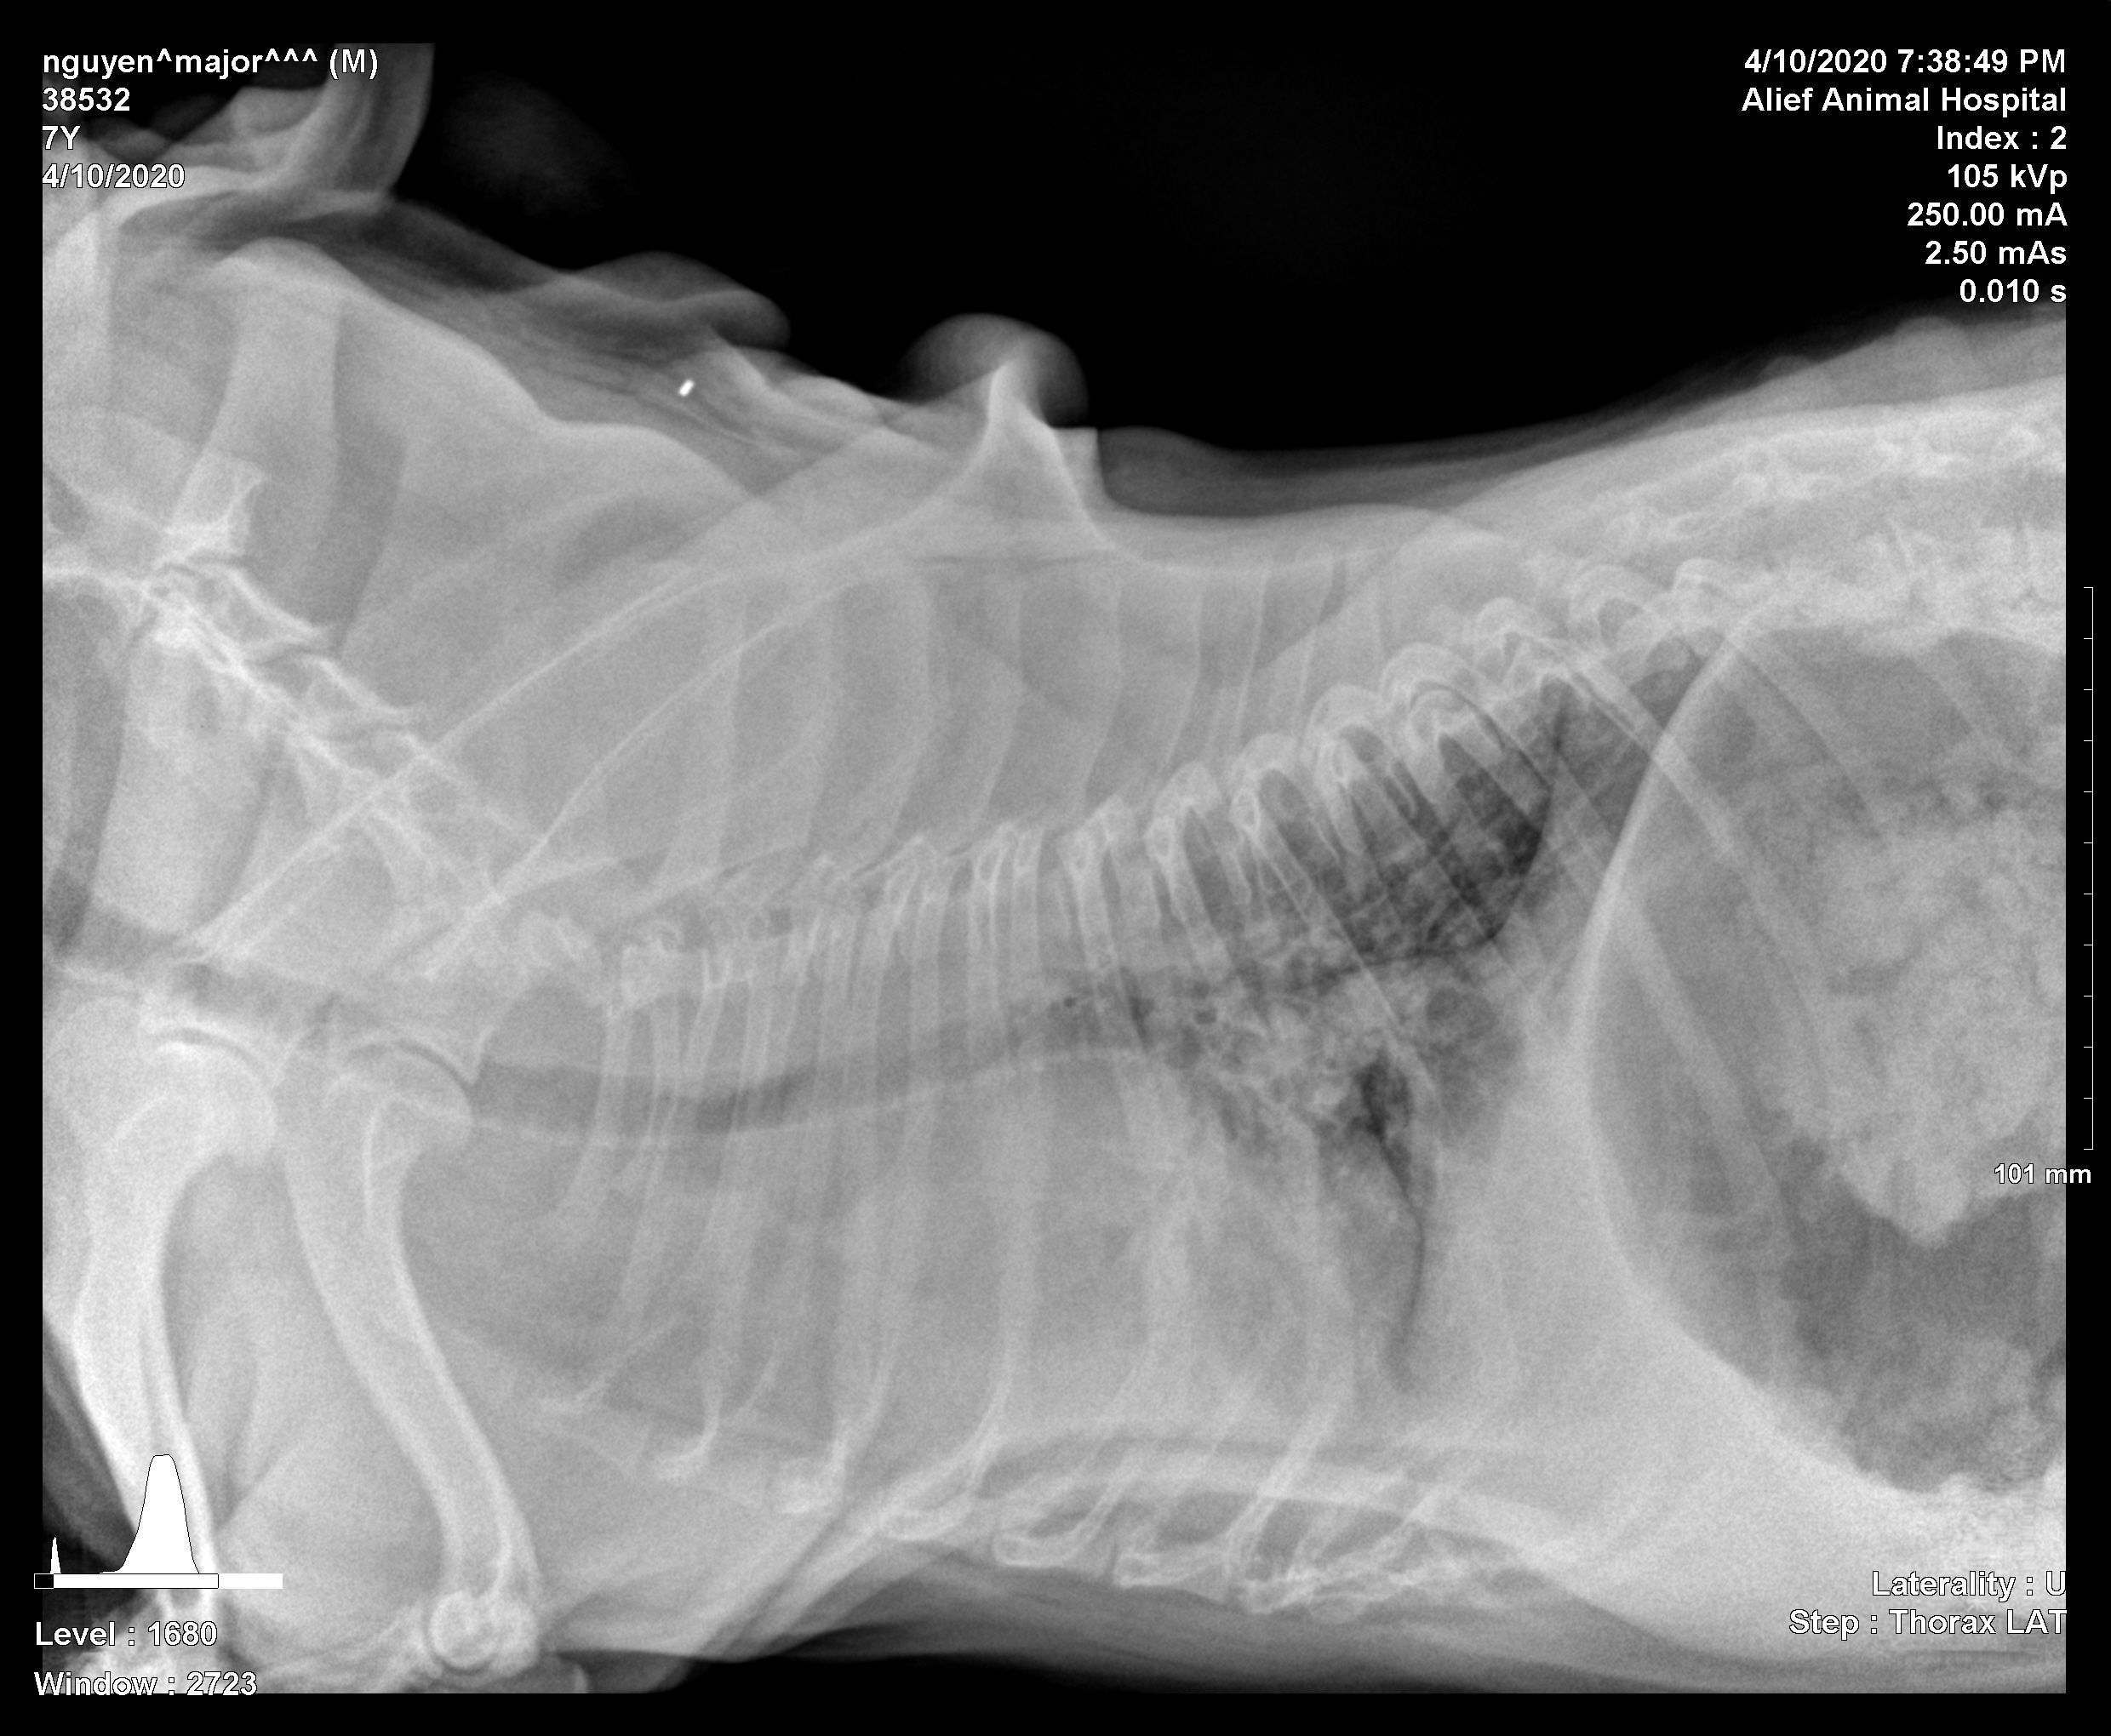

Major been gagging/coughing all day so took him to the vet,

He got diagnosed with ( lung lesions, cranial lung field soft tissue density, enlarged heart areas of spondylosis dedormans observed), white blood counts at 17. Plus lower back arthritis . He's also been dealing with dry eyes n losing vision both of his eyes.